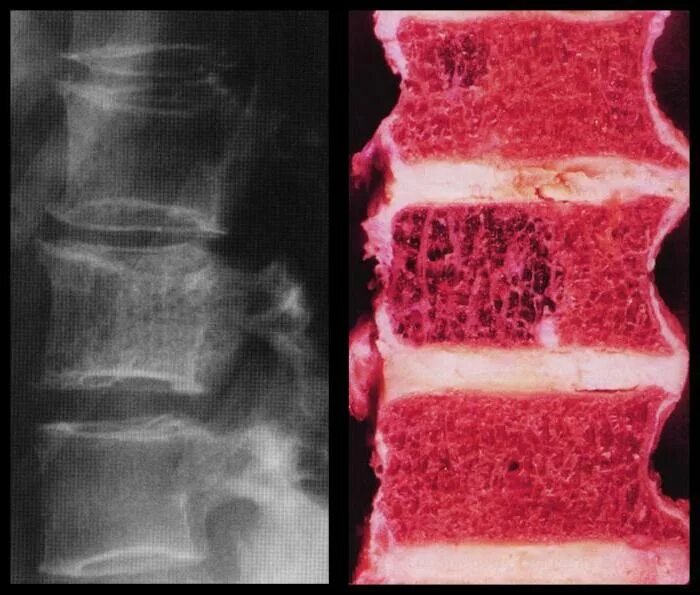

Симптомы рака позвоночника грудного отдела